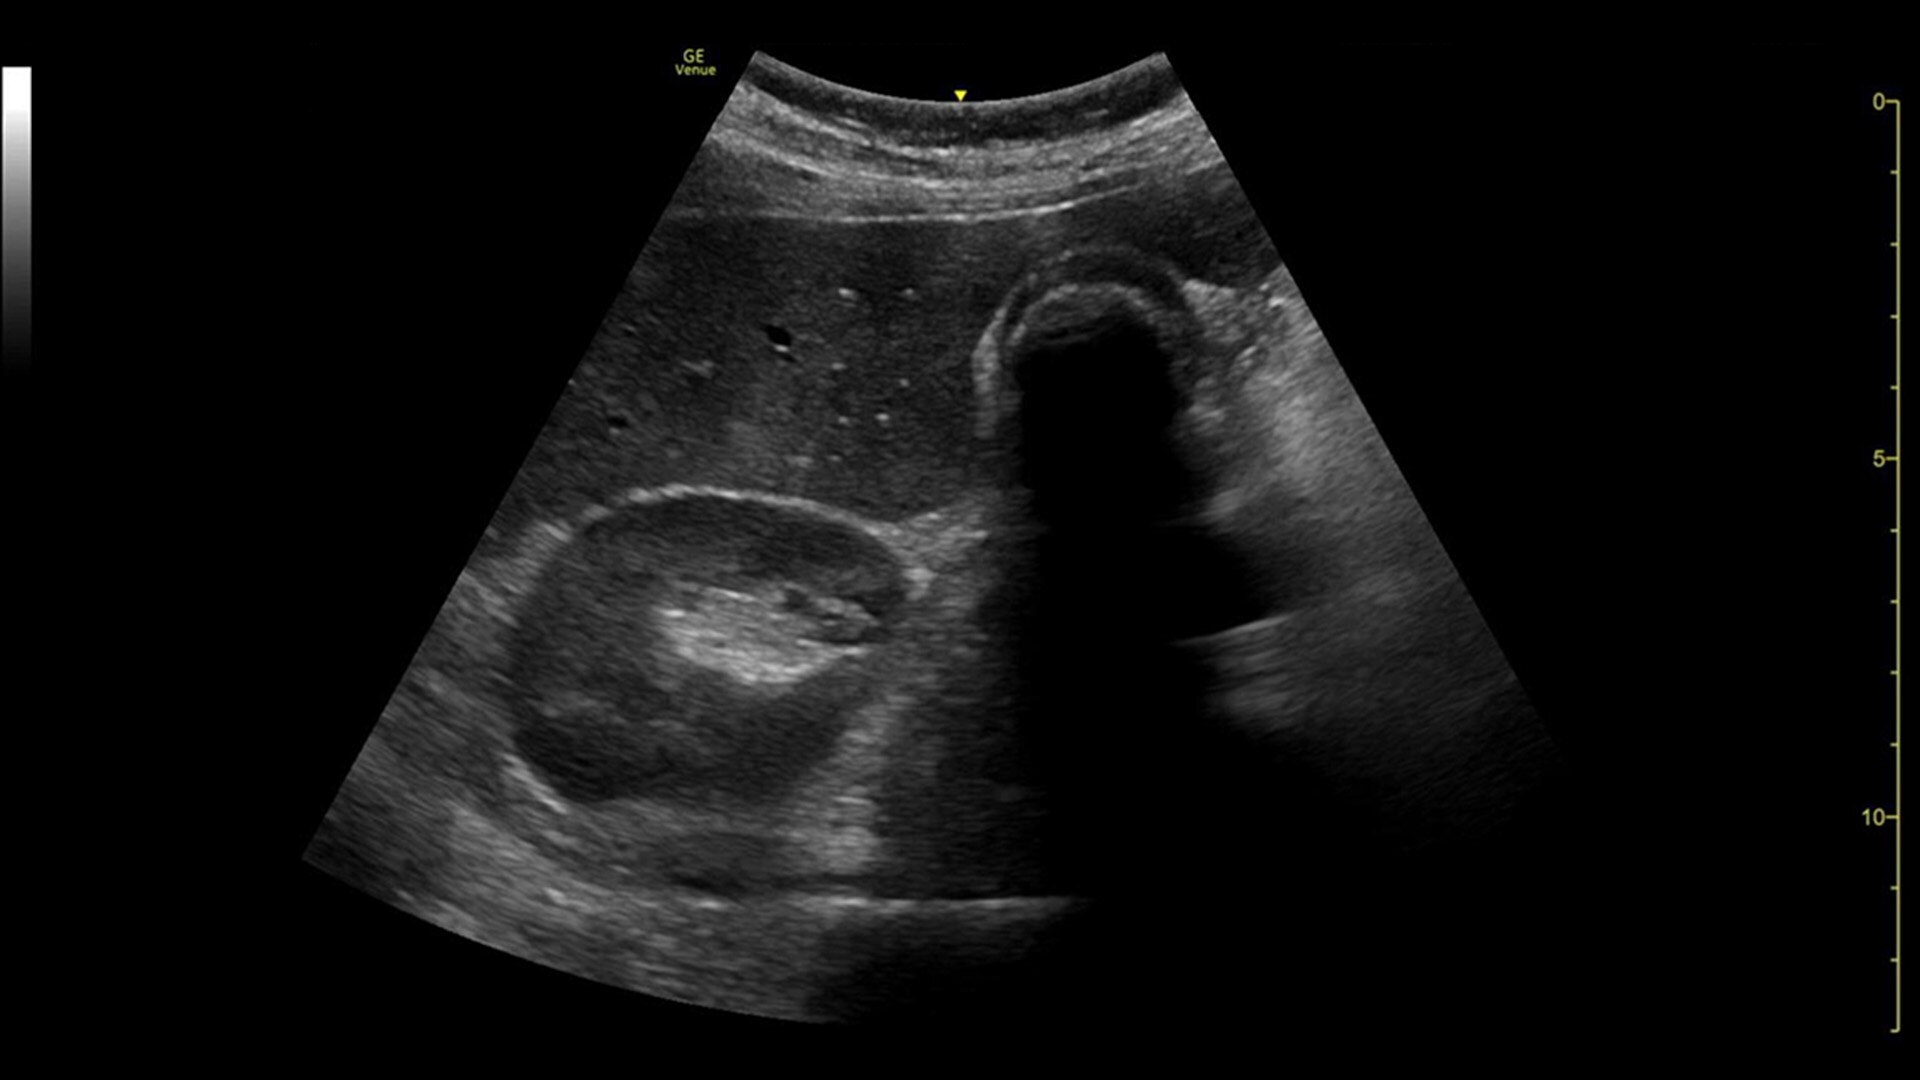

Quickly assess kidneys and the bladder with Renal Diagram

Simplify documentation and provide easy follow up for patients with suspected hydronephrosis. No need to type findings; simply assign a label from a pre-populated list that correlates with images.